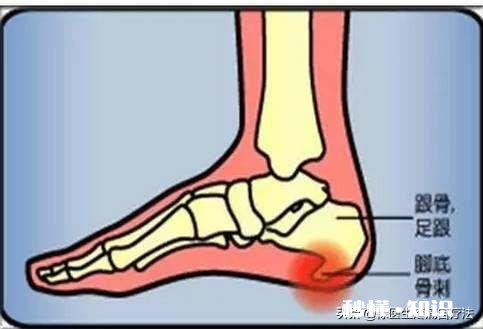

足底筋膜,在我们的脚底,从跟骨往前延伸到脚趾下,把我们的脚趾都往上翘,能摸到脚底变硬了,那就是我们的足底筋膜 。当我们的脚趾往上翘的时候,附着在跟骨下方的肌腱是被往前拉的,时间久了,骨刺就被拉出来了!这才是足底骨刺的最大原因!

足底筋膜从后跟往前延伸到脚趾下方 。

跟骨的骨刺大多数都不是垂直向下的,而是往前的 。所以骨刺怎么会扎到肉里呢?